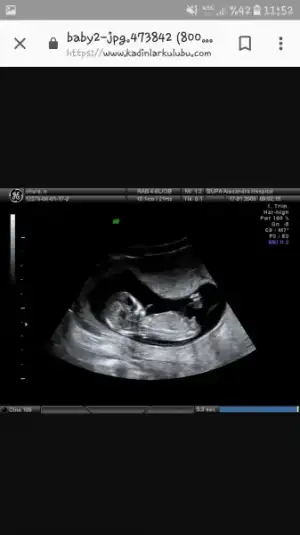

morceket morceket ayrıca genital nub cıkıntısana gore de paralel gözüküyor Kız gibi sağlıklı bi evladın olur inşallah :)

Ayrıca genital nub teorisini merak edenler kk da böyle bir konu var bakın isterseniz ben okdar cok ultrason vıdeosu cınsıyet tahmını vıdeosu ızledım kı doktordan once soylerım dıye korkuyorum :D :D

Merak edenlere. Cinsiyet teorisi. 11.Haftadan itibaren net görülebilir. :) Screenshot_20180623-115200.webp Screenshot_20180623-115259.webp Screenshot_20180623-115323.webp 2. fotoğraf erkek, 3. kız. %99 ihtimal doğru olduğu söyleniyor. :)

Eki Görüntüle 2160356 11+6'dan herkese selamlarr. :) Doktora çarşamba gitmiştik. İkili test için 45 mm olması lazımmış. 3 gün önce 43 küsürdü. Şimdi 51 mm olmuş. :) İkili test için kan verdim, 1 hafta sonra çıkıyormuş. Bebeğimin hareketlerini de ilk kez gördük. Çokkkkk güzeldi. :))))) Ayaklarının birini havaya kaldırıyor diğerini indiriyordu. :))))))